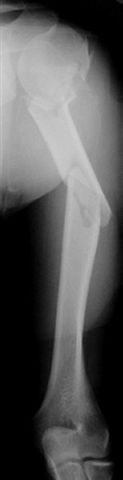

Многооскольчатый перелом плеча

Мужчина 35 лет доставлен к нам через неделю после автотравмы - был в машине. Получил перелом вертлужной впадины (надо оперировать) и открытый многооскольчатый перелом плеча

(рана по преденей поверхности 5 см, ушита неделю назад - сейчас все спокойно), по поводу которого и вопрос - что с таким повреждением делать? Снимок кладу один, поскольку на втором практически та же проекция. Заранее спасибо.

Если я не ошибаюсь, плечо фрагментировано на шесть (!) отломков, и если "про оперативную фиксацию мысли как-то не успокаиваются..." -- металла может потребоваться очень много.

That is the worst humerus I have seen.

This IS a terrible fracture, are the neuro-vascular bundles OK? With respect, Dr Salvi's approach is "classical AO thinking", from a country where the Ilizarov technique was first used outside Siberia! Cattani, Cataneo, etc, must be most upset that their teaching is being forgotten already...Even the AO giants would not do the classical approach here, I think.

With an open, comminuted fracture of the humerus, the option chosen must respect the soft tissues, or an infected non-union will be the result. I would chose either a hybrid Ilizarov-type fixation, with half-pins proximally and wires distally, or a locked IM nail.

Although we can not see exactly the head piece, and assuming that there are not signs of infection, my suggestion would be to do some type of "bridging" procedure : implant fixation in head piece and distal main fragment, and the rest to be left on its soft tissue attachments (living bone graft).

I just did this attached case, using 90 degrees angled blade plate, and this would be my preference in all similar cases.